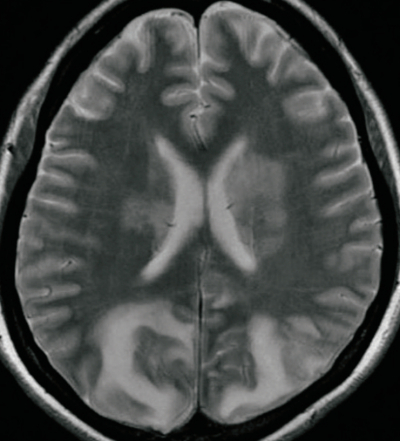

搬入時の意識レベルは JCS Ⅰ-2。けいれんは治まっていた。体温 37.2 ℃。心拍数 82/分。血圧 164/96 mmHg。呼吸数 20/分。 SpO₂ 96%(マスク 5L/分酸素投与下) 。頭部MRIの T2強調像及び拡散強調像とを別に示す。

この患者の脳にみられる病態はどれか。

e. 浮腫